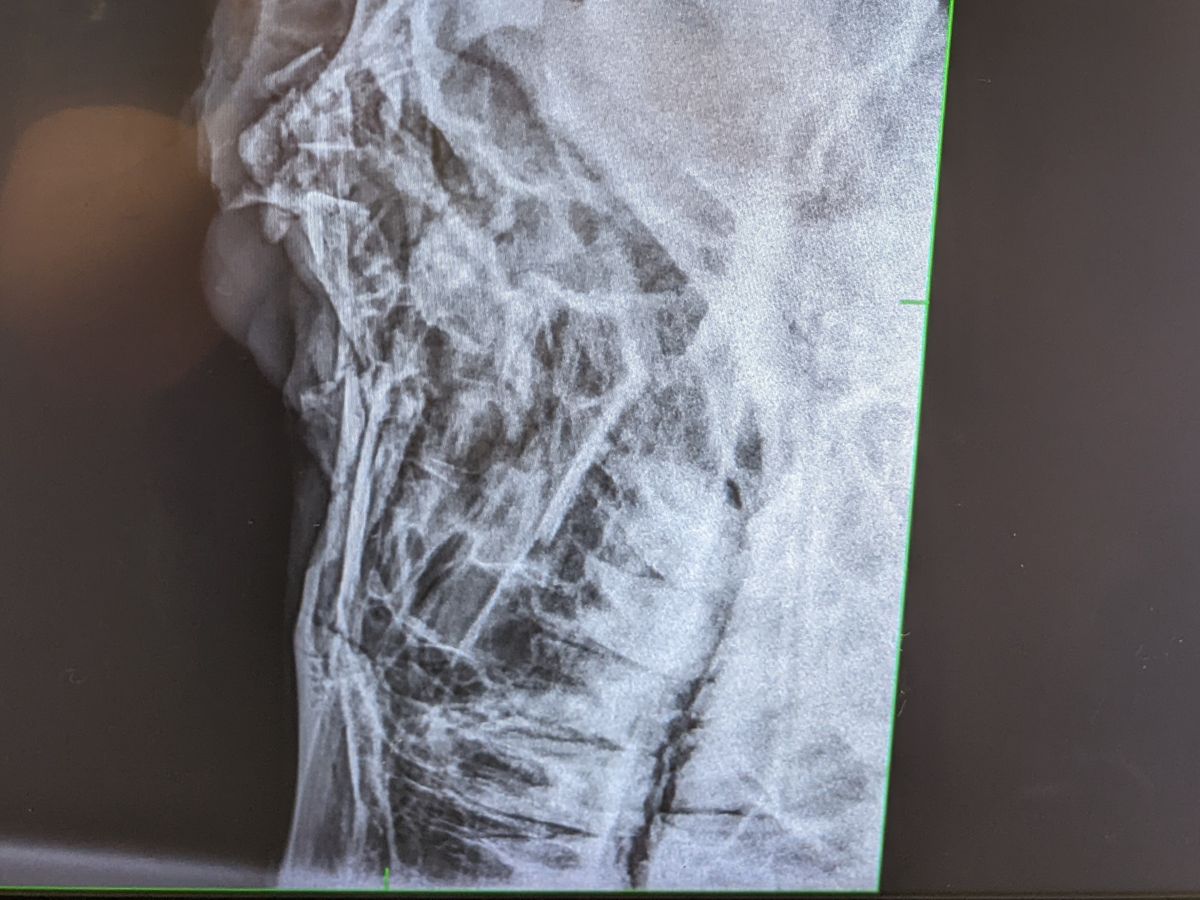

On 6/18/22, near 11:30 PM, a faulty gate lock let him and other horses out of a wooded acre+ paddock. The horses crossed and ran down the insanely (almost interstate-worthy) busy highway. The other horses made it to safety and were caught. King did not. It was a two-hour search before he was found with his skull partially crushed from being hit by a vehicle. The driver left, but the debris was left behind.

King must have his right eye removed and have reconstruction surgery. After surgery, board, and medication it will likely cost around $2000...But that is an early estimate that could change depending on what happens.